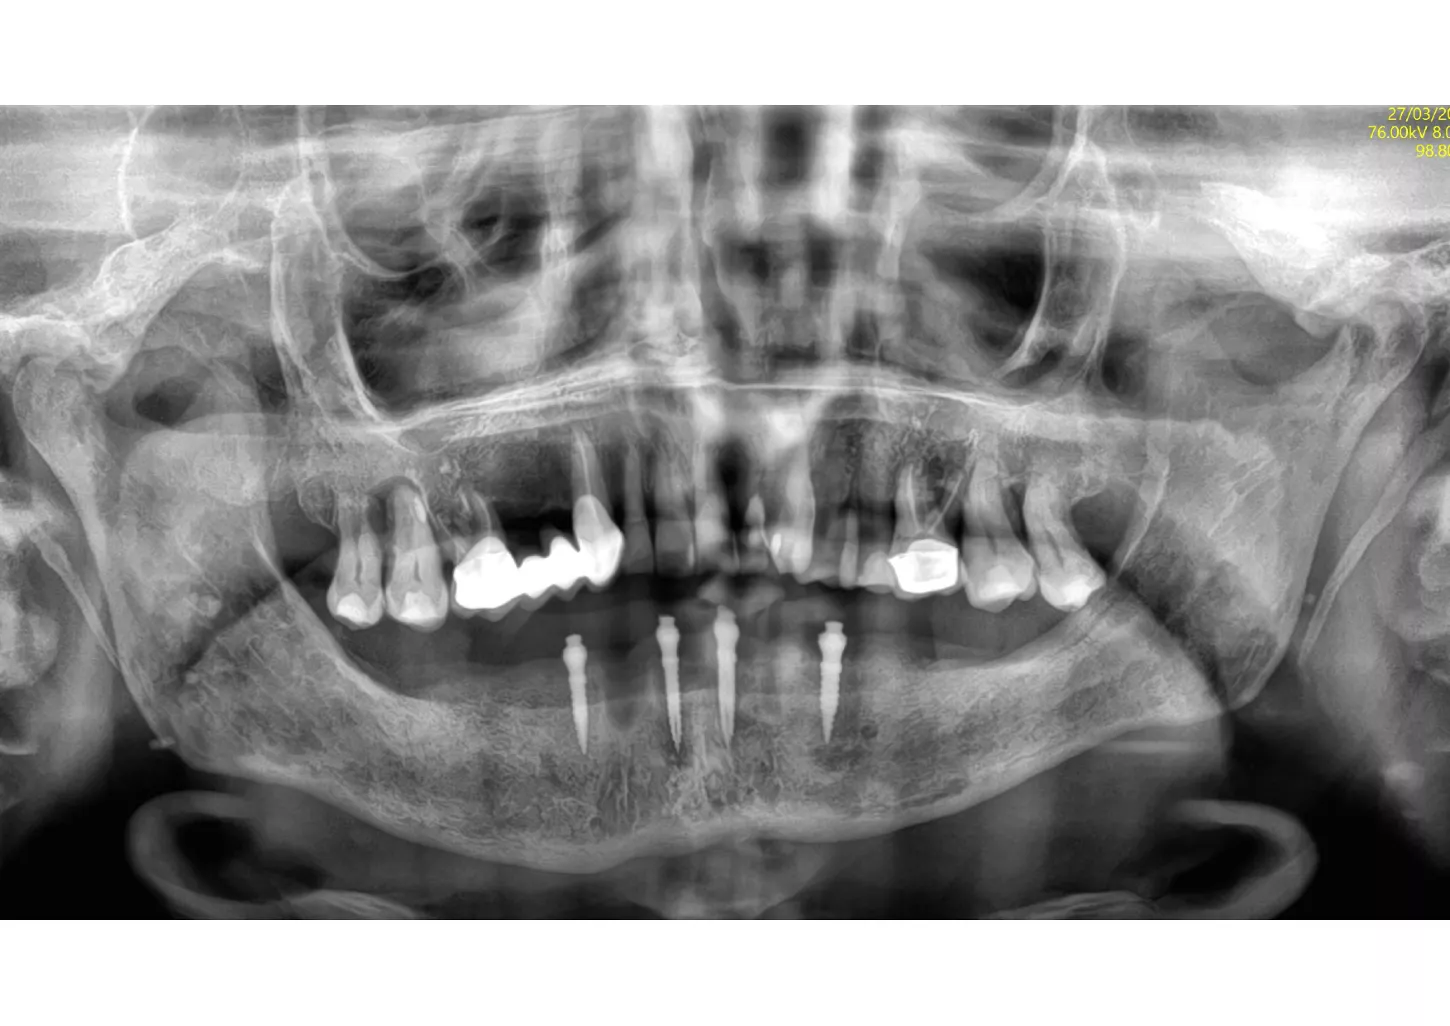

1a. 1b. Pre-operative panoramic X-ray and CBCT showing moderate generalised bone resorption in the mandible, a reduction in vertical dimension in the posterior region and the planned positioning of mini- implants.

1a

1b